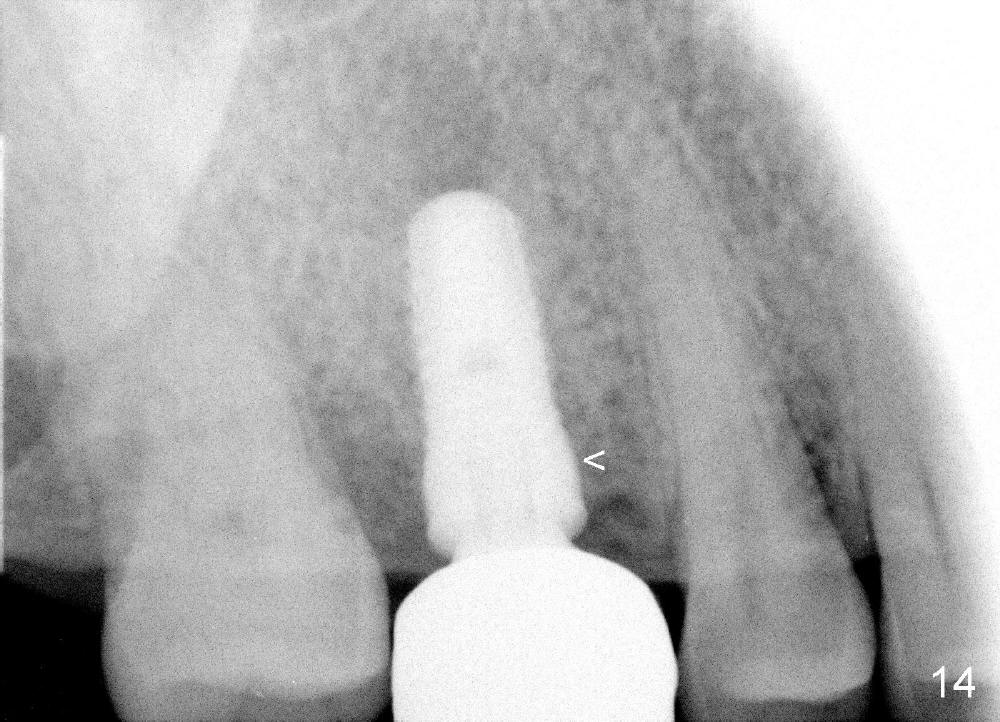

The tooth #3 has a crack line (Fig.1 ^). The septum (Fig.2 S) looks like an inverted pyramid (Fig.3), coronal part being pointed, whereas the apical broad. The shape of the septum is not so favorable to placement of tapered implant. Osteotomy starts with 1.5 mm pilot drill in the middle of the septum, followed by round tapered osteotomes 2 and 3 mm. The osteotomy begins to deviate into the mesiobuccal socket. The same osteotomes are used to re-direct the osteotomy palatally, followed by tapered drills, trying to move osteotomy palatally. A 4.5x17 mm tap is inserted with stability (Fig.4). Following using 5x17 mm tap at the depth of 12 mm, a 5.3x12 mm bone-level implant is placed ~ 1.5 mm below the crest, 1.5 mm above the septum (Fig.5). Demineralized cortical human allograft is placed in the remaining sockets and around the most coronal aspect of the implant (with a small piece of gauze placed in the implant well). After removal of the gauze, a piece of collagen membrane is pierced and carried by a 8.2x4/3 mm healing abutment and fixed in place (Fig.6 M). The periphery of the membrane is tucked underneath the gingiva. The wound is covered by perio dressing. The patient returns to clinic for follow up 8 days postop. There is no discomfort. In order to protect the collagen membrane (Fig.6), the perio dressing is intentionally not removed (Fig.7). Two weeks postop, the patient remains asymptomatic. After perio dressing removal, the membrane appears to have been resorbed (Fig.8 as compared to Fig.6). The bone graft (B), although exposed, remains in place and condensed, surrounded by healing healthy gingiva (*). The patient returns 2.5 months postop. The implant appears to osteointegrate (Fig.9, as compared to Fig.5). The buccal (Fig.10) and palatal (Fig.11) gingiva adapts to the healing abutment. When the healing abutment is removed for restoration 3 months postop, the gingiva looks healthy (Fig.12). A cemented abutment (5.8x4(2) mm) is placed; a crown is fabricated (Fig.13). The patient returns for recall 5 months post cementation. He reports food impaction distal to the crown. The gap mesial to the implant has closed (Fig.14).

The crowns at #3 and 14 have been cemented for 3 years 2 months and 2 years 2 months, respectively (Fig.15).